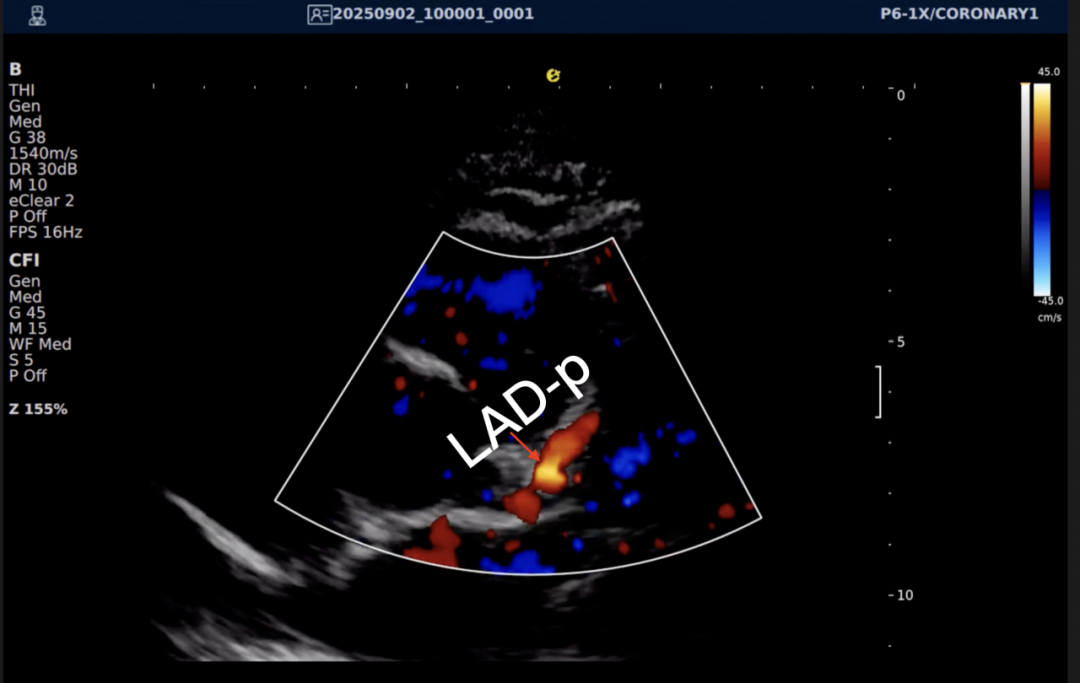

以下为逸超医疗(ESI)设备采集的冠脉图像,清晰展示了其在二维成像、彩色多普勒及频谱多普勒方面的表现:

左右滑动查看更多

心脏冠脉超声

一例胸闷患者,临床采用无创冠脉超声作为初步评估手段,检查中发现:

彩色多普勒:敏感捕捉到局部血流加速现象;频谱多普勒:测得峰值血流速度明显升高,频谱形态异常。

基于超声提示的异常发现,临床为患者安排了冠脉CTA检查,结果显示前降支近段存在约45%狭窄,与超声提示的血流动力学改变高度一致。